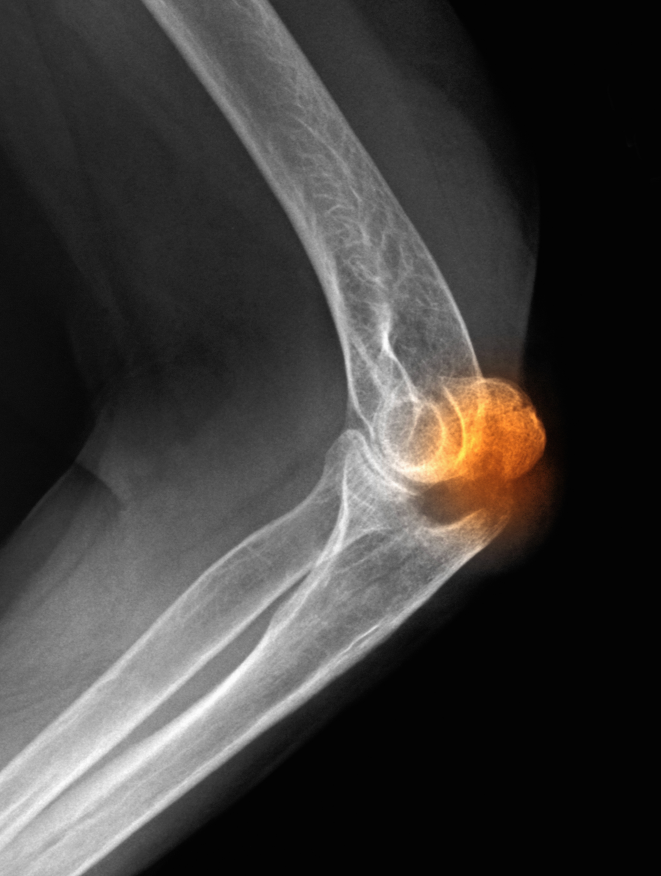

尺骨鹰嘴骨折发生率约占全身骨折的1.17%,是一种关节内损伤,因此常伴随关节内积血和组织液渗出。患者表现为肘关节疼痛、肿胀及活动受限,同时骨折端可触及凹陷。该骨折最重要的体征为抗重力伸肘丧失,表明伸肌装置连续性中断。该体征对治疗方案至关重要,在临床上往往需结合X线来明确诊断。

此外,对于尺骨鹰嘴骨折患者,应详细检查其上肢神经功能,尤其需排除尺神经损伤。尺骨鹰嘴骨折伴随肘关节的屈伸,骨折端很容易分离移位,且鹰嘴半月切迹关节面的缺损或者不平整会引起后期肘关节僵硬或创伤性骨关节炎。术中对半月切迹良好的复位和固定是治疗尺骨鹰嘴骨折的基本原则。尺骨鹰嘴骨折无移位或者移位<2mm的患者可以尝试非手术治疗。其主要适用于无移位且稳定的骨折,一般采用屈肘90°石膏或者支具固定。